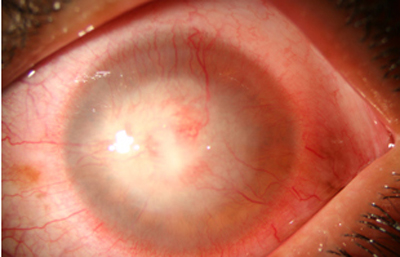

Superficie corneal irregular y grisácea, (Fig. 1, 2) con opácidades granulares en parche y formación de líneas epiteliales elevadas de aspecto granular (Fig. 3), que pueden arborizar dando imágenes de pseudodendritas. Opacidades superficiales satélites. (Figura 4) Inyección ciliar. Ulceración epitelial variante. (Figura 5).

Acanthamoeba Síntomas de 25 días evolución

Fig. 2 Síntomas de 25 días evolución